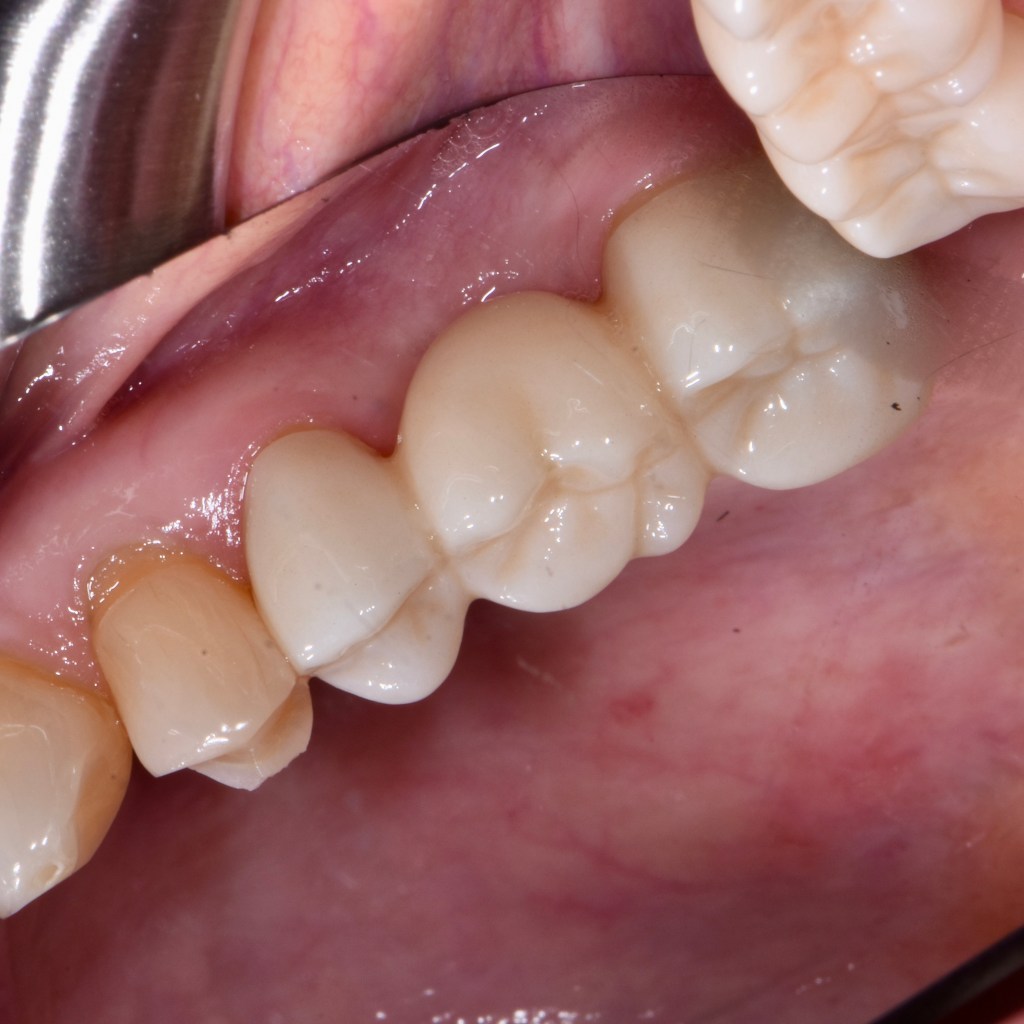

Custom Ceramic Crown

Custom Ceramic Crowns